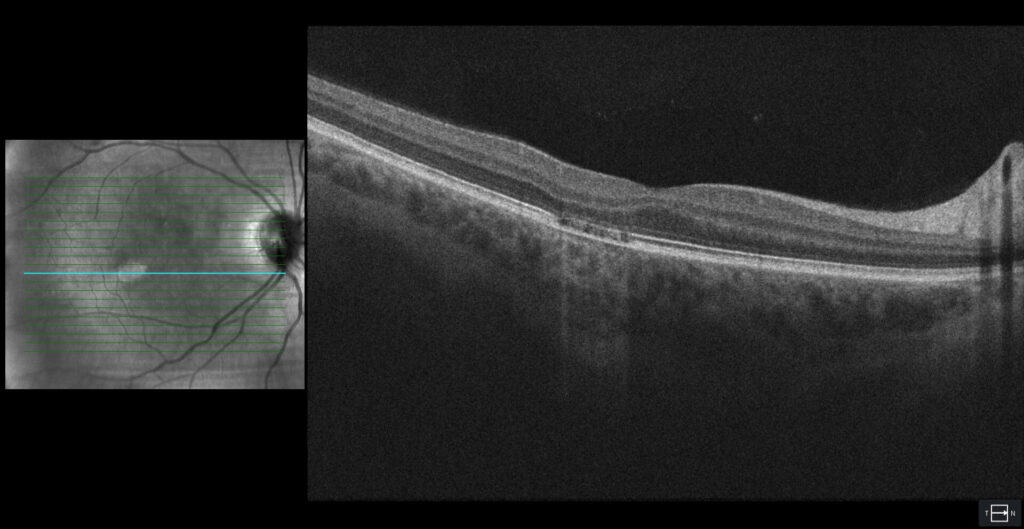

OCT imaging revealed attenuation of both the ellipsoid and interdigitation zone (Figure 2). The underlying Bruch’s membrane was flat without breaks. The choroid appeared grossly intact, and the foveal ellipsoid zone was spared. There was no evidence of either subretinal or intraretinal fluid.

Increased access to OCT imaging has allowed for these lesions to be further quantified into type 1 or type 2 lesions. In both types, there is attenuation of the ellipsoid zone and interdigitation zone. Type 2 lesions are defined by also having outer retinal cavitations, whereas type 1 lesions do not display this finding. Excavation may or may not be present in both lesion types.7 Microperimetry testing often displays a dense scotoma associated with both lesion types. Our patient’s lesion would be classified as type 1 given the lack of cavitation.